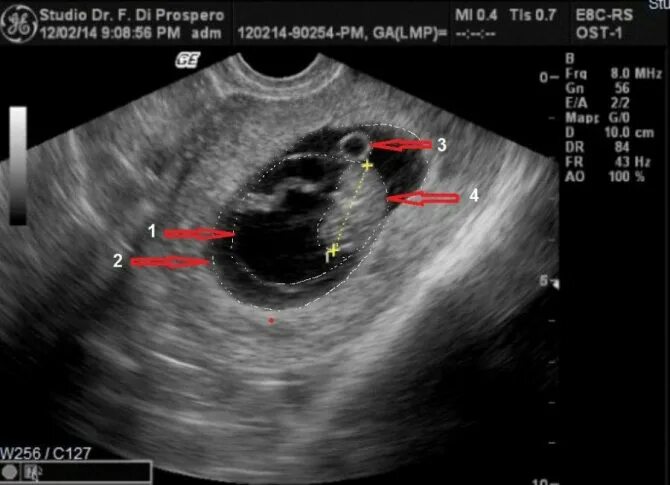

9 5 неделя беременности